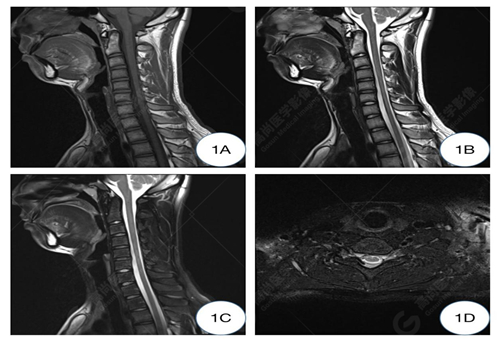

1A-1C圖、常規(guī)仰臥位T1WI及T2WI矢狀位圖示頸椎生理曲度變直,椎體形態(tài)及信號(hào)均正常,椎間隙正常,椎管未見狹窄;1D圖、常規(guī)仰臥位T2WI橫軸位示C5-6水平硬膜外間隙未見增寬,相應(yīng)水平頸髓未見受壓。